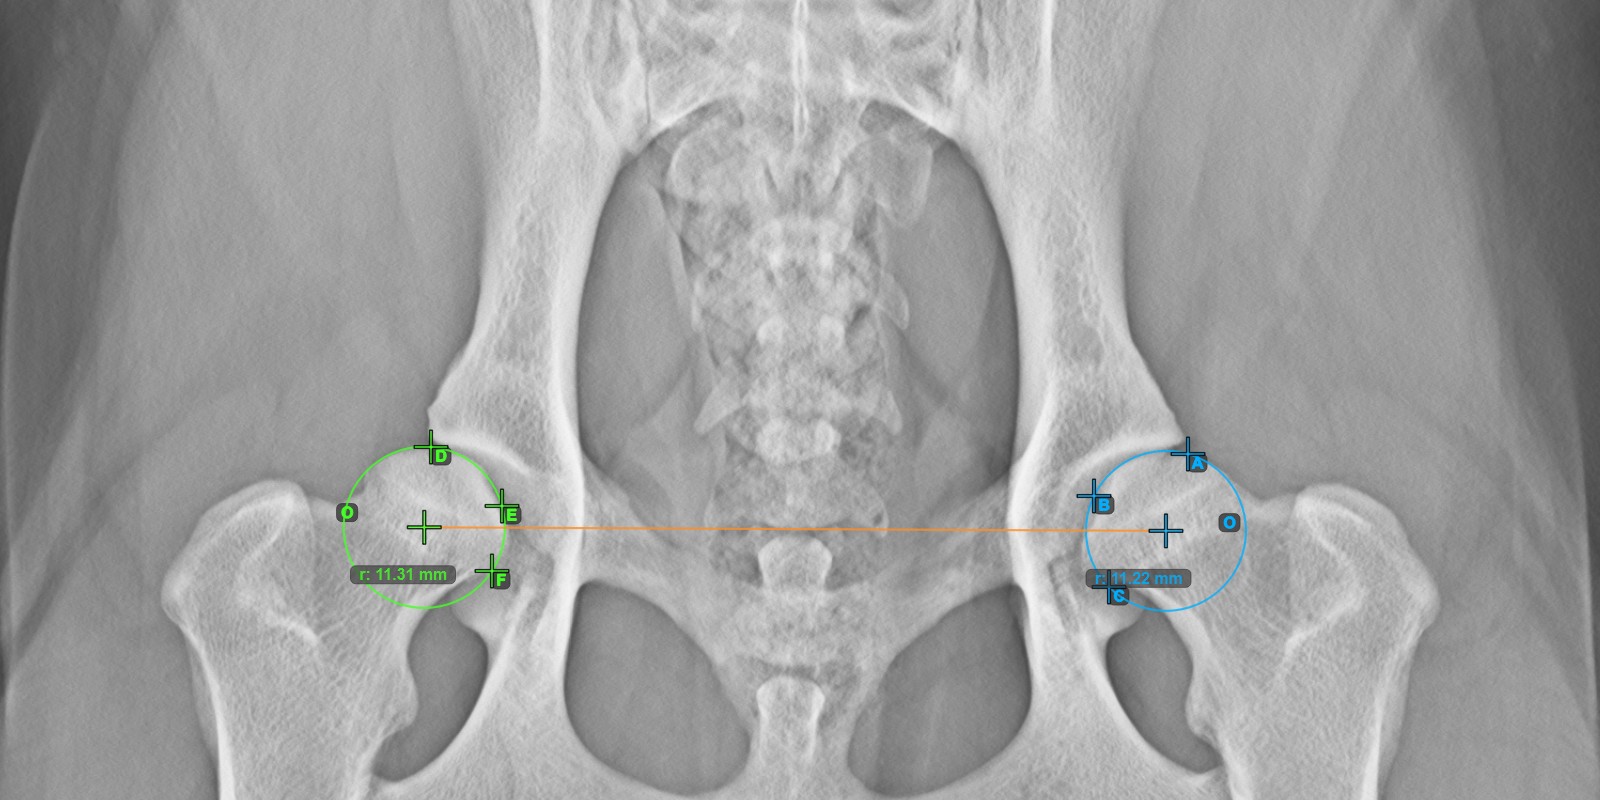

Calculate the left Norberg Angle measurement by marking a line on the effective edge of the left Acetabularis bone.

Mark a point near the left Caput Femoris and drag it along the effective edge of the left Acetabularis bone, forming the terminal side of the left Norberg Angle.

The drawn line must be a tangent to the effective edge of the left Acetabularis bone. The value and arc of the angle is automatically calculated.

The image below depicts the typical placement of the line and the calculated Norberg Angle measurement.